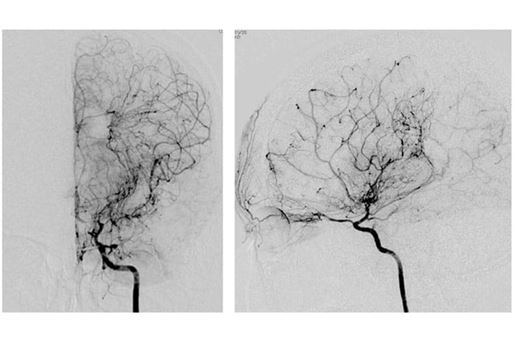

suzuki digital subtraction angiography

• Adult moyamoya disease and syndrome is a rare disorder characterized by an abnormal formation of abnormal network of dilated and fragile blood vessels in the brain. It is a heritable disease and carries a significant morbidity and mortality.